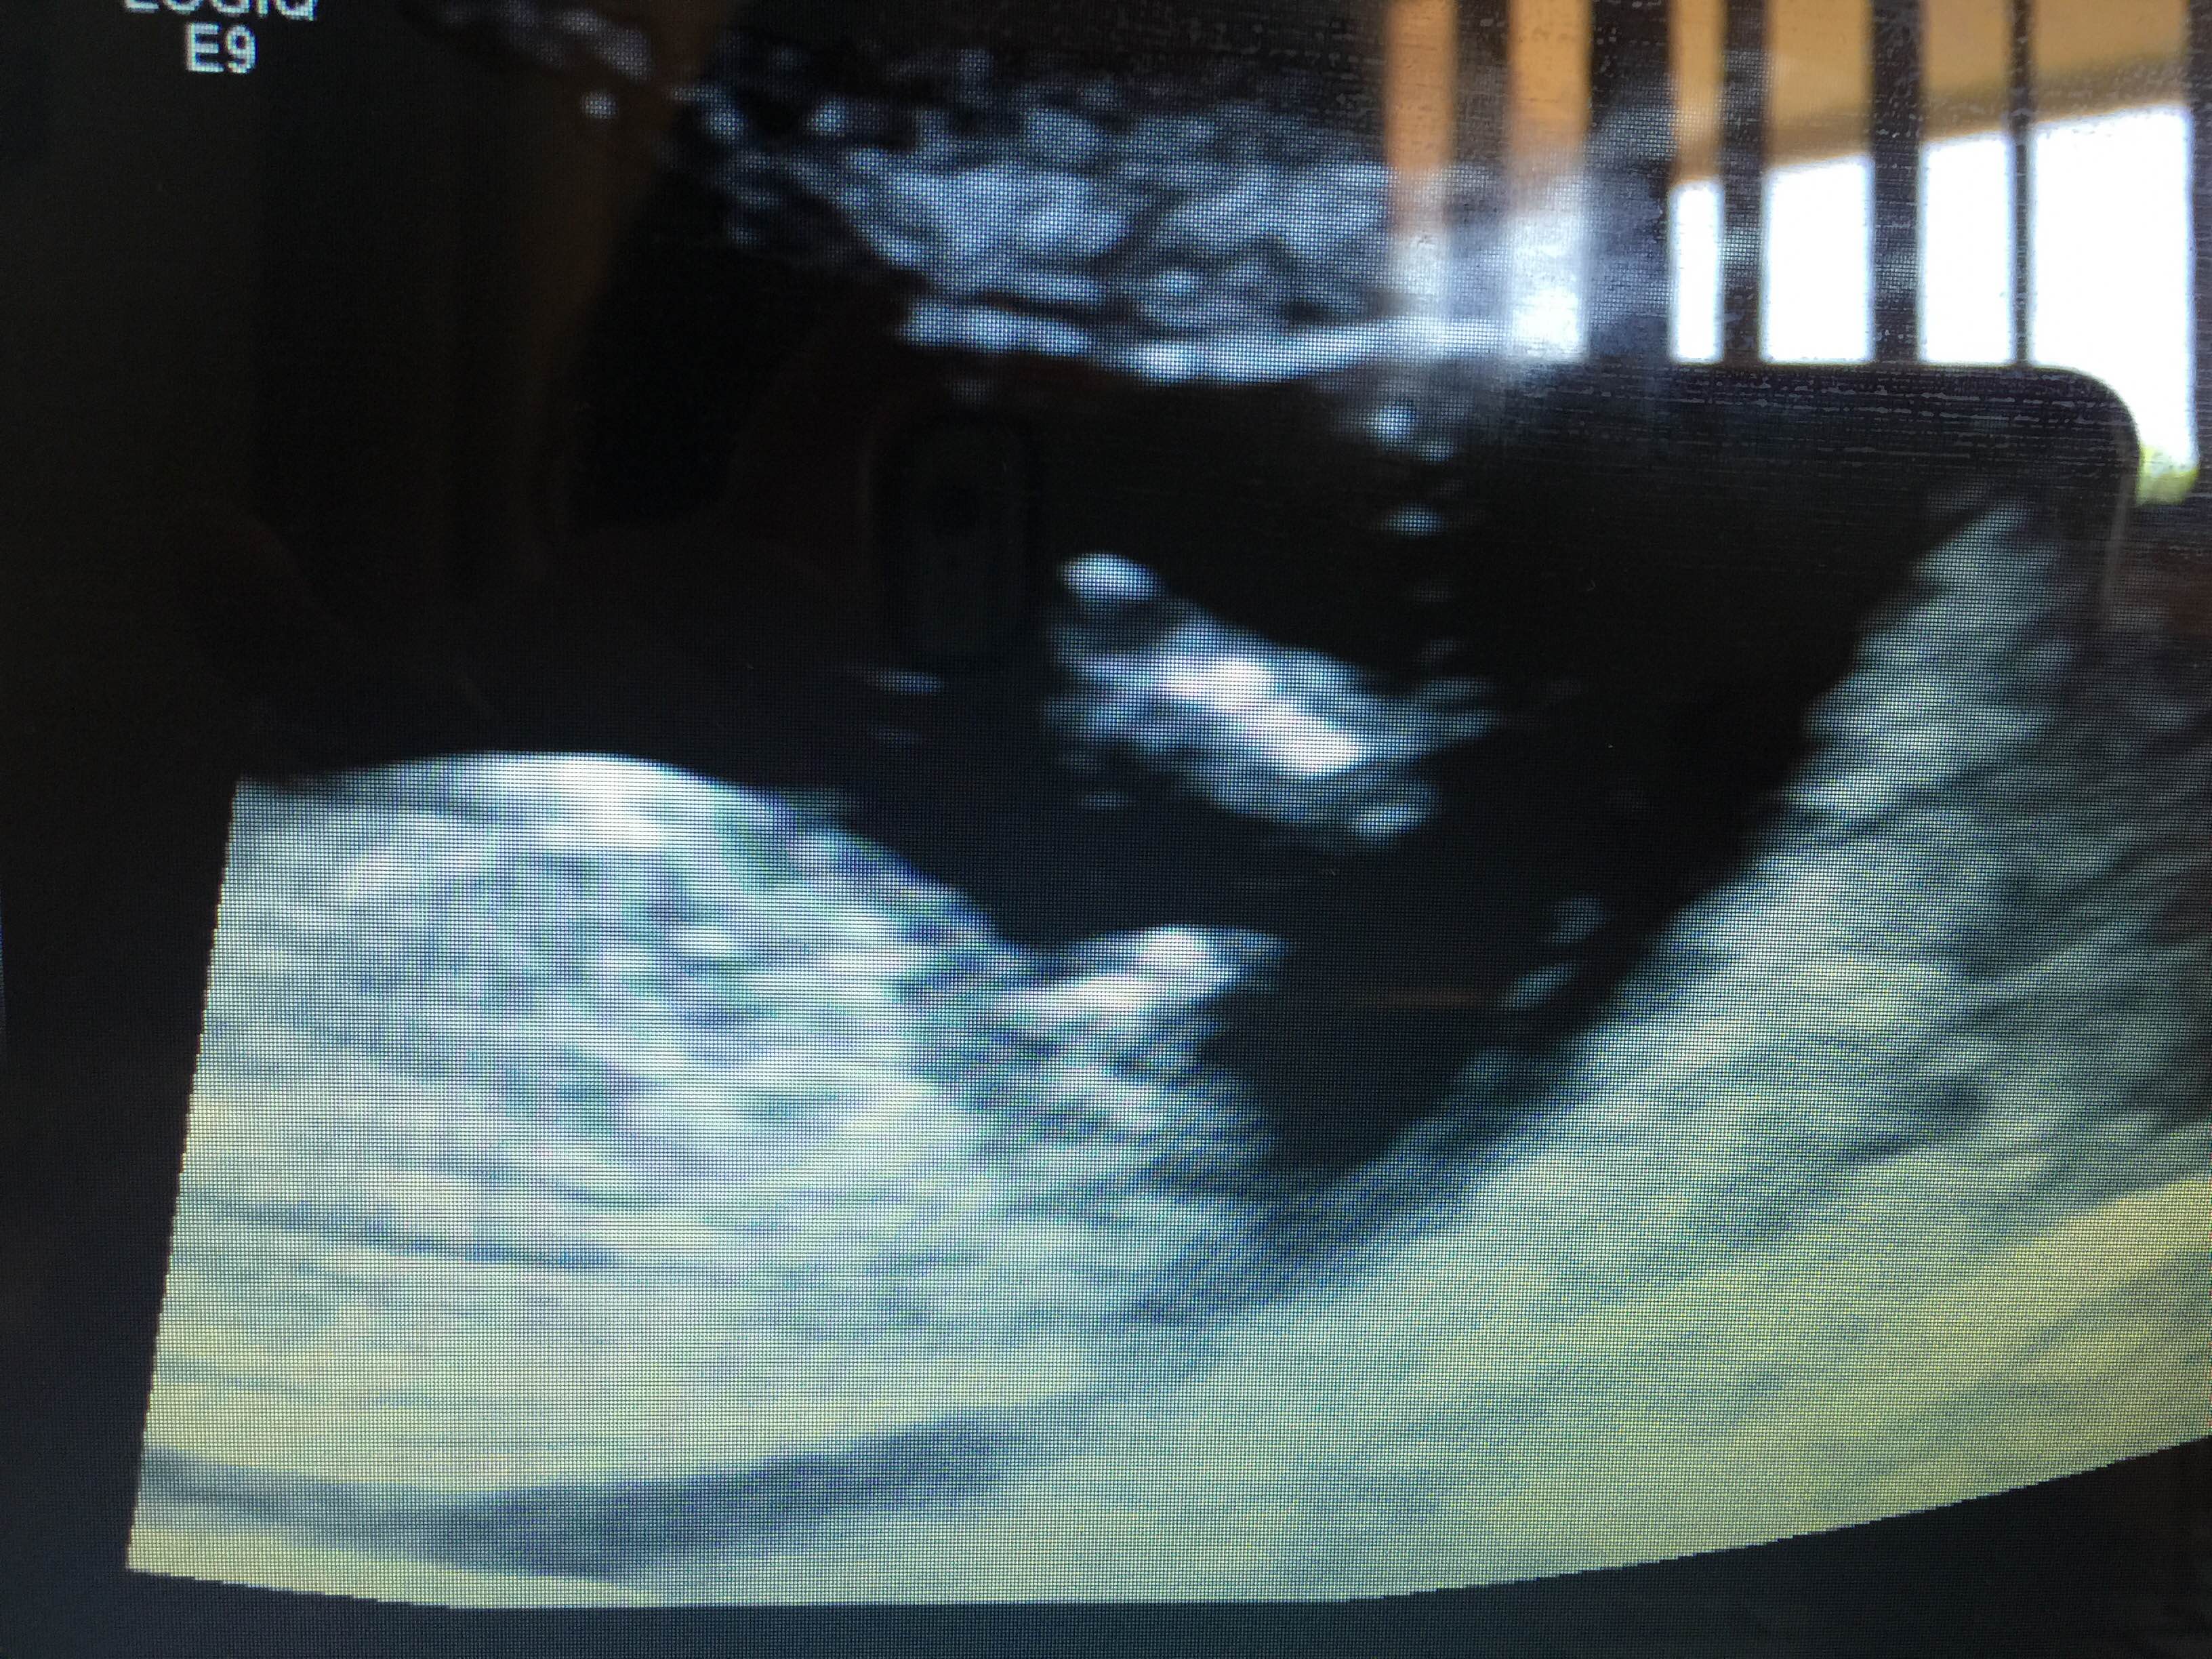

If thats a nub i see in the 3rd pic id say a little boy.

Boy guess from the 3rd pic, but the first 2 look girly to me. Leaning boy!

Boy lean from me

Looks like a boy! Congrats!